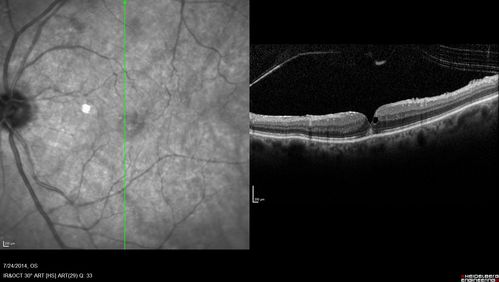

Macular Hole Left Eye - progression from VMT - Stage II macular hole - Spontaneously Closed Macular Hole

Vision has improved to 20/40 and the hole is closed